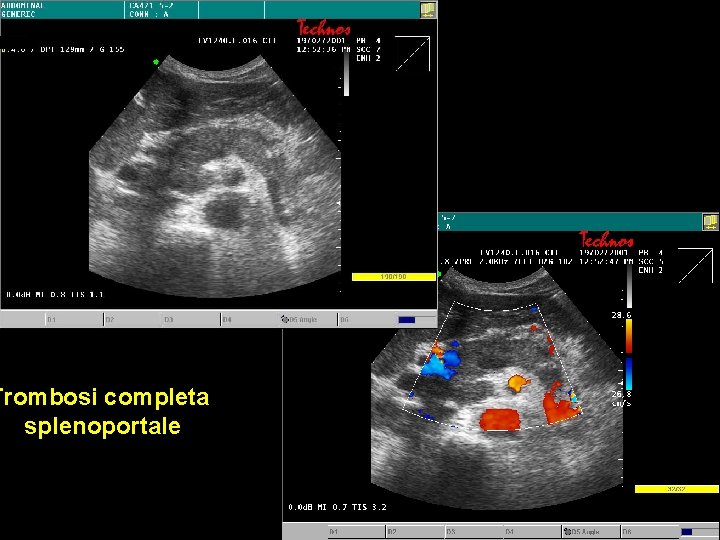

Trombosi ramo portale destro Trombo

Trombosi completa splenoportale